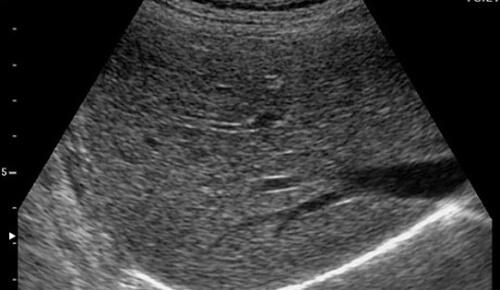

- B超

有的人说 , 我检查过肝功能和乙肝两对半 , 为什么还要做B超?因为它们看问题的角度是不一样的 。

血液检查一般来说看的是功能 , 而影像学检查我们可以直接看到结构 。